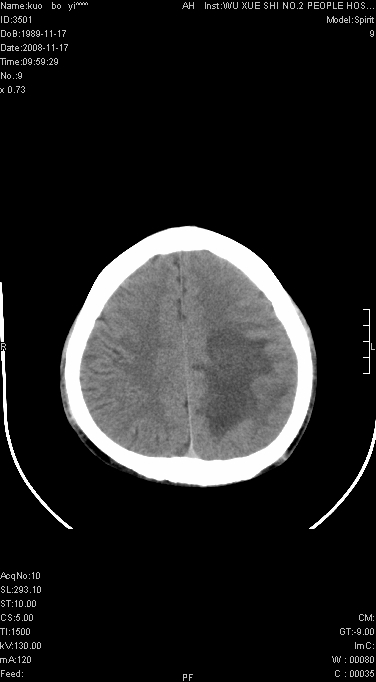

右侧肢体无力一周

这么大片面积,中线居中,占位效应不明显,考虑脑梗塞。

灶中央有厚环状高密度成分,顶叶皮质局部有显著的受压表现,多支持占位性病变,胶质瘤?淋巴瘤?转移?不知患者年龄多大,病史较短,不除外炎性

左顶叶较大范围水肿区,内见明显强化的片状 棉絮状组织,但占位效应不明显。多考虑:脑炎!

还是考虑原发脑胶质瘤,梗塞缺血水肿的低密度要同时累及皮、髓质并要符合动脉供血的区域分界特点,本例强化后见瘤体结节及向周围浸润生长的瘤血管都强化了,水肿广泛呈指状,占位效应使同侧脑皮质受压变薄、脑沟消失但因实质性的瘤体尚小所以中线无明显移位。不知各位同意这样分析吗?(转移瘤多为多处病灶)

首先考虑脑胶质瘤。有明显的左顶叶脑白质水肿,病变轻度占位效应,花环样强化,脑炎——影像不支持!

左顶叶大范围水肿,内见明显强化的片状 棉絮状组织,但占位效应不明显。考虑脑炎可能性大。

不像脑梗死,低密度区中心,有一密度增高边界清楚的,近脑组织密度的病灶.建议进一步强化及肺和肝等重要脏器检查.